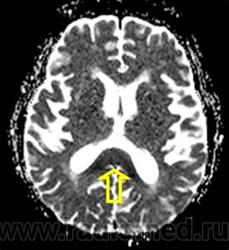

Marchiafava, 1897, Bignami, 1903 – редко встречающийся вариант алкогольной энцефалопатии с патологистологичнски проявляющимся поражением (некрозом) мозолистого тела, образованием полостей в ткани мозга и развитием внутренней гидроцефалией. Клинически активная фаза заболевания длится от 2 до 6 лет, завершается она формированием глубокого слабоумия. В психотической стадии болезни наблюдаются слуховые и зрительные галлюцинации, апатия, депрессия, припадки, состояния возбуждения, спутанность сознания, картины псевдопаралича, а также разнообразные неврологические симптомы (тремор рук, дизартрия, абазия, арефлексия или гиперрефлексия, ослабление зрачковых реакций, изменение формы и величины зрачков и мн.др.). Лечение симптоматическое. Синонимы: Дегенерация мозолистого тела, Прогрессирующая алкогольная деменция